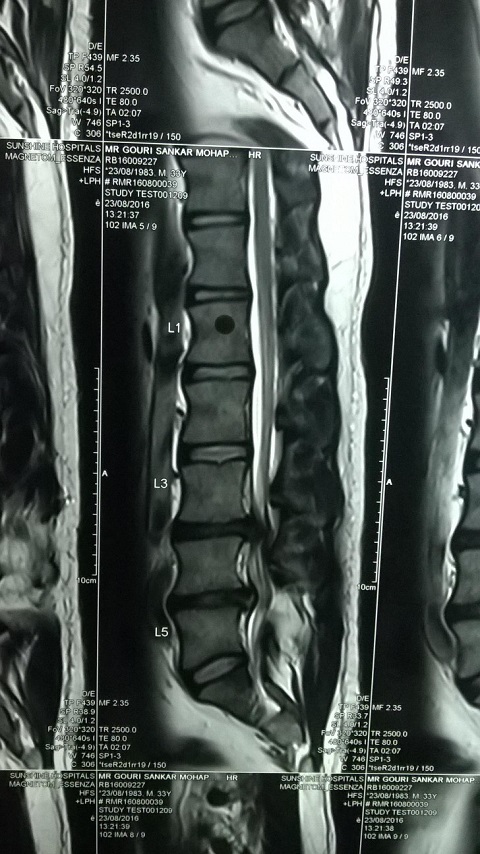

X-Ray of Ramesh Chandra Moharana